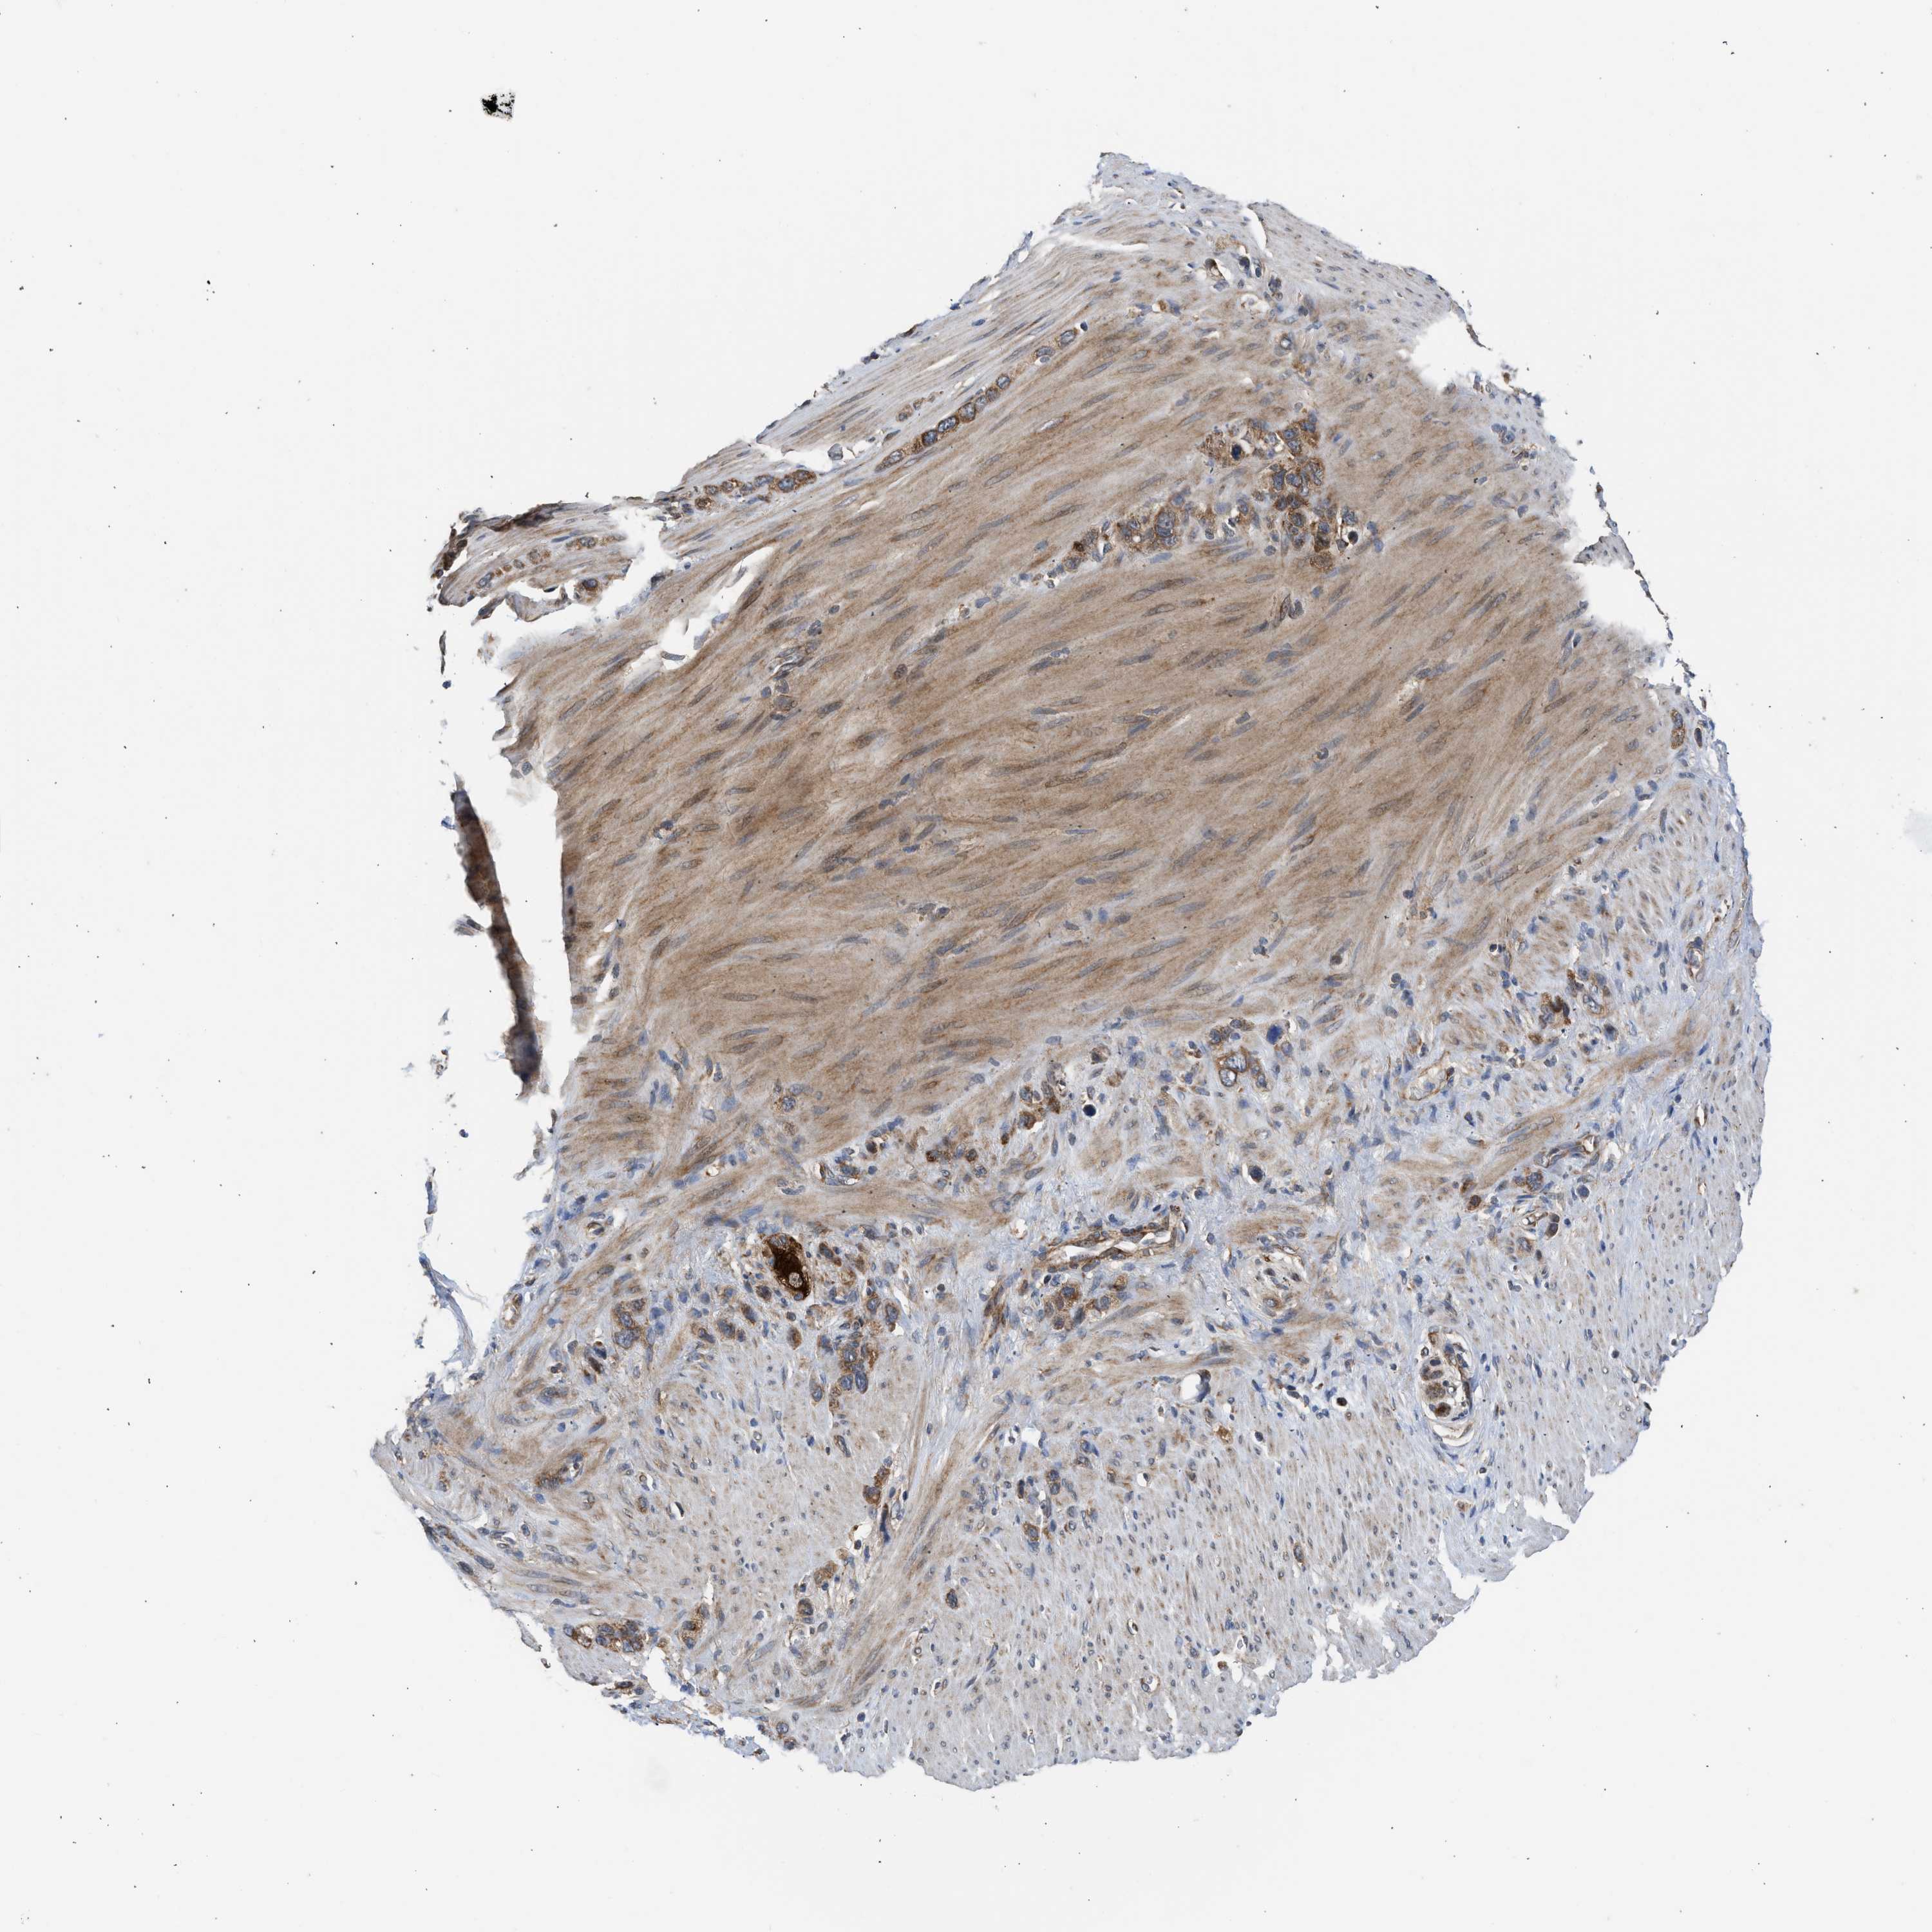

STOMACH CANCER - Protein expressioni

A mouse-over function shows sample information and annotation data. Click on an image to view it in a full screen mode. Samples can be filtered based on level of antibody staining by selecting one or several of the following categories: high, medium, low and not detected. The assay and annotation is described here.

Note that samples used for immunohistochemistry by the Human Protein Atlas do not correspond to samples in the TCGA dataset.

Antibody stainingi

Antibody staining in the annotated cell types in the current human tissue is reported as not detected, low, medium, or high, based on conventional immunohistochemistry profiling in selected tissues. This score is based on the combination of the staining intensity and fraction of stained cells.

Each image is clickable and will lead to virtual microscopy that enables deeper exploration of all samples and also displays staining intensity scores, fraction scores and subcellular localization as well as patient and tissue information for each sample.

Antibody HPA023202

Antibody CAB017030

Staining

High

Medium

Low

Not detected

Intensity

Strong

Moderate

Weak

Negative

Quantity

>75%

75%-25%

<25%

None

Location

Nuclear

Cytoplasmic/membranous

Cytoplasmic/membranous,nuclear

Adenocarcinoma, NOS

Adenocarcinoma, High grade